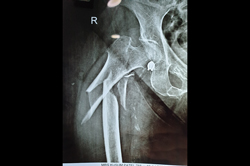

Neck Femur Fracture